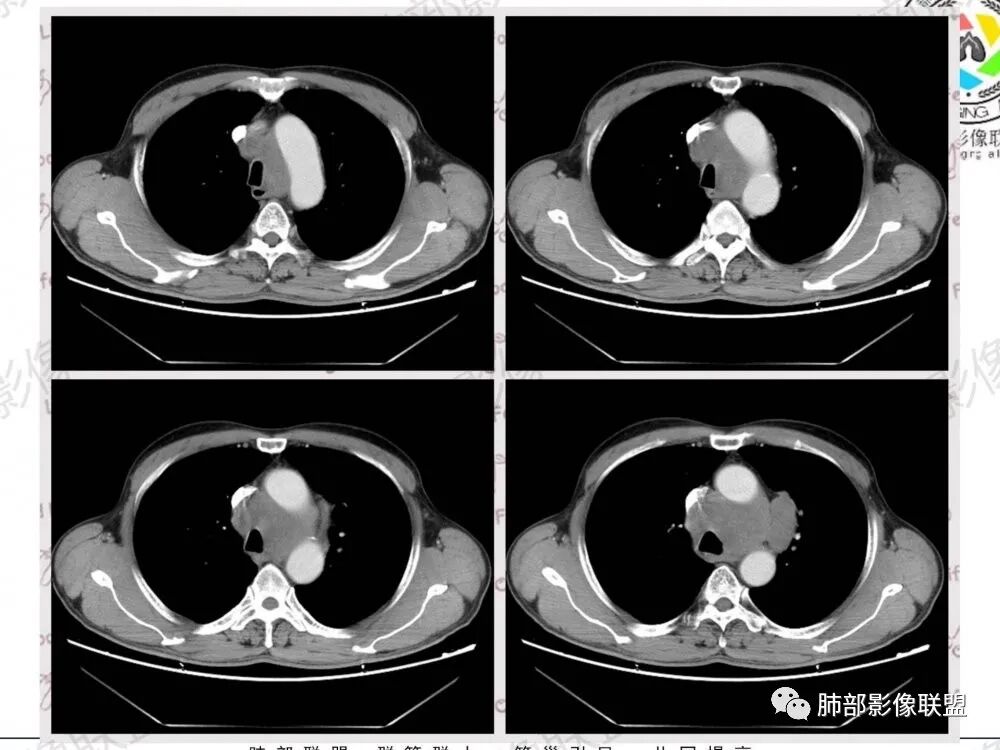

57岁男性,长期吸烟史,有血吸虫病史,有粉尘接触史。发现纵隔淋巴结肿大2年,声嘶伴咳嗽咳痰半月。两年前胸部CT见左上肺尖后段结节并肺门淋巴结肿大,治疗后左上肺结节消失。目前胸部CT:肺气肿,左上肺尖后段见条索影(原来结节治疗后的改变?),肺门、纵隔淋巴结肿大并融合,似见薄壁包膜样强化。考虑淋巴结结核可能性大,注意鉴别淋巴瘤、转移、结节病等。

男性,57岁,发现纵膈淋巴结肿大,现声嘶伴咳嗽咳痰。COPD背景,纵隔内、左肺门多发肿大淋巴结相互融合,冰冻纵隔?增强后轻度强化,主气管向右侧推移。考虑肺癌,小。

纵膈、左肺门多发增大淋巴结,部分融合,增强强化不明显,首先考虑小细胞癌转移,鉴别淋巴瘤。

纵膈及左肺门多发肿大淋巴结,部分融合呈团块状,密度不均,增强后轻度边缘强化,考虑转移,鉴别淋巴结结核

位移:

纵隔及左肺门多发肿大淋巴结,融合团块状,密度不均,增强后轻度边缘强化,中央似有坏死,考虑转移瘤,鉴别淋巴瘤

影像特点:

1.左肺门及纵隔见异常增大淋巴结,部分融合,不均匀轻度强化,未见明显坏死。

肿大淋巴结与纵隔血管等结构“无缝”贴合。

2.纵隔增宽但依旧居中。